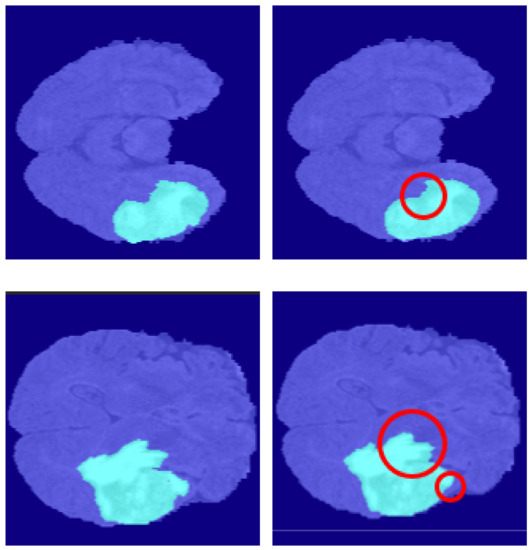

5.6.1. Segmentation Boundary Loss

5.6.2. Third Dimensional Information Loss